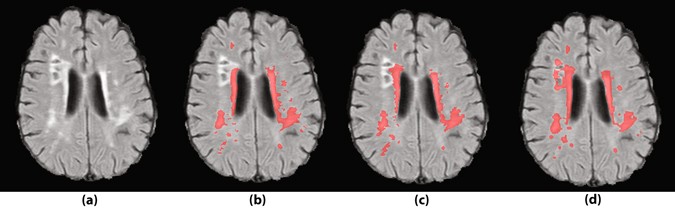

Figure 7

Gliosis around the lacunes is a prevalent type of false positive segmentation. (a) FLAIR images without annotations. (b) Segmentation by human observer 1. (c) Segmentation by human observer 2. (d) Segmentation by MSWS + Loc method.